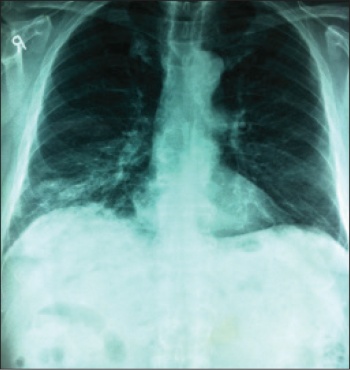

Figure 1. Initial CXR on presentation

Figure 1. Initial CXR on presentation(click to enlarge)

This had previously been carried out for what was thought to be right middle-lobe pneumonia. Infiltrates were displayed at the chest x-ray (see Figure 1). The patient had not responded to two courses of antibiotics prescribed by the GP for right middle-lobe pneumonia. He was initially noticed to be cyanotic by the nursing staff during triage even though he denied being breathless but admitted being uncomfortable. The procedure was cancelled and the patient was admitted to hospital.